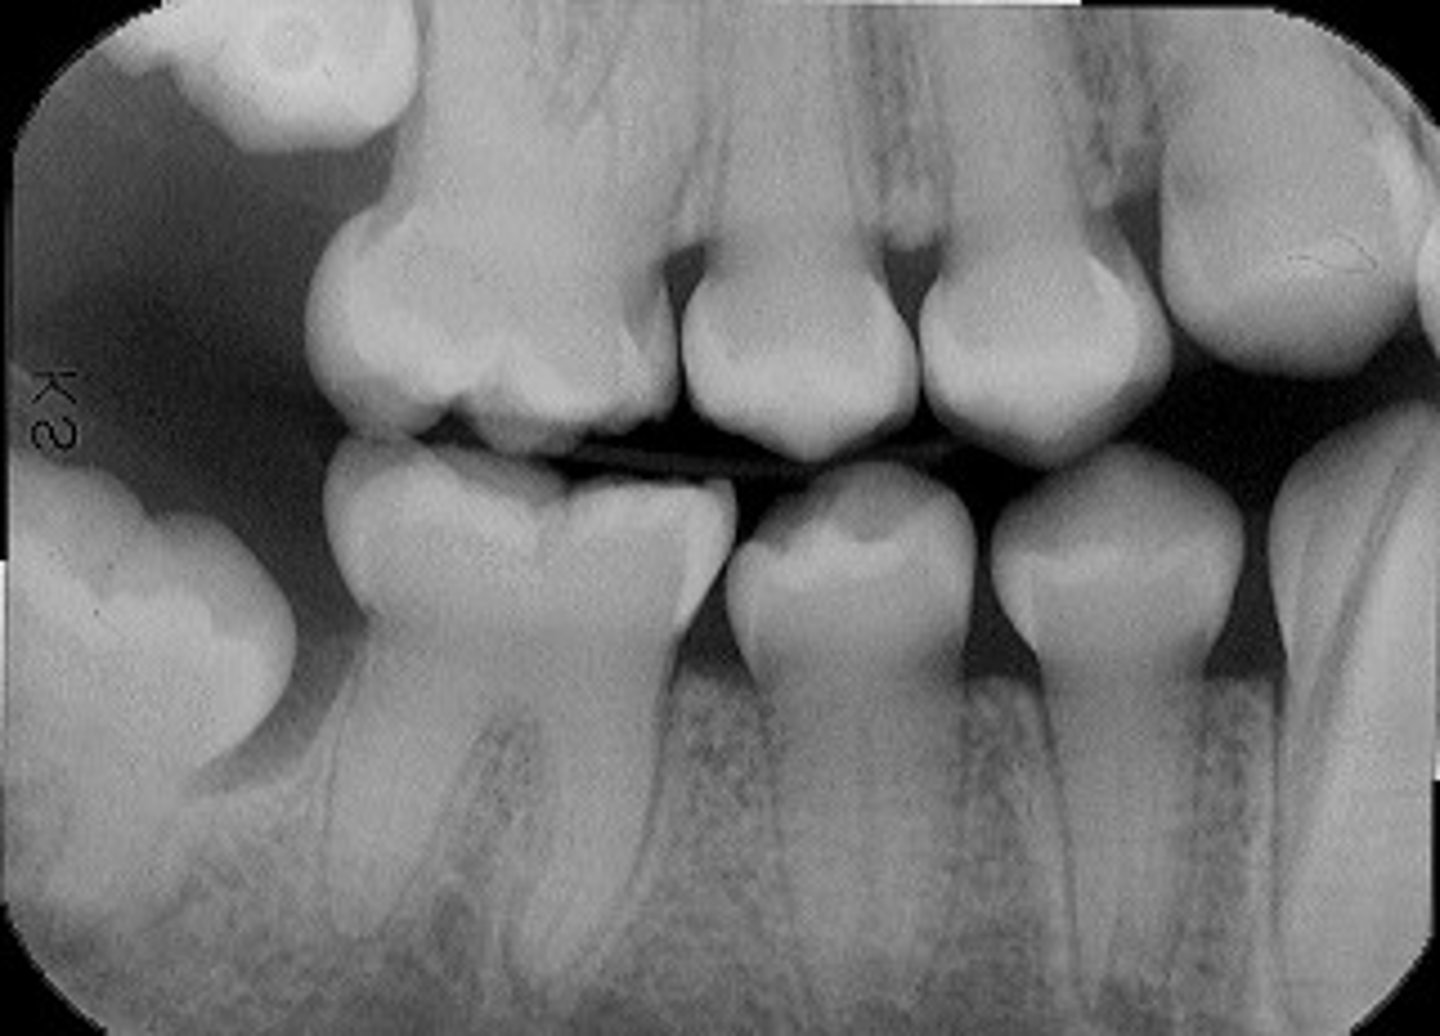

-Roots → very short roots = "rootless"

-Crown color → normal

-Crown shape → normal

-Pulp → obliterated + large pulp stones

**MULTIPLE periapical radiolucencies